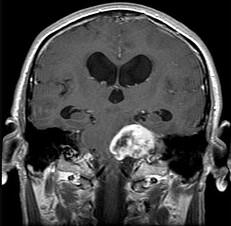

问题 听神经瘤(如图所示)的最常见症状为()

选项 A.头痛、呕吐 B.面部麻木,痛觉减退 C.眩晕,单侧耳鸣,耳聋 D.吞咽困难,进食呛咳 E.小脑运动共济失调

答案 C